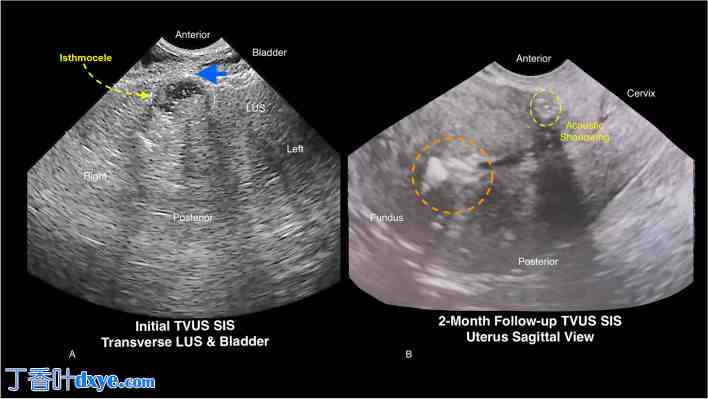

二维经阴道超声 (2D-TVUS) 显示子宫前峡部有一 10 毫米的透声腔,提示存在峡部膨出。术前二维经阴道超声及生理盐水灌注宫腔声学造影 (SIS) 证实子宫肌层残留厚度 (RMT) 缺失,且子宫内膜腔变形,提示 Asherman 综合征(图 1A)可能由既往子宫内膜消融术引起。

图 1.

二维经阴道盆腔超声 (2D-TVUS) 及 SIS。A. 术前子宫下段 (LUS) 和膀胱二维经阴道超声及 SIS 检查显示,一个 10 毫米的峡部膨出已延伸至膀胱后黏膜(蓝色箭头),且子宫肌层残留厚度 (RMT) 缺失。 B. 术后2个月二维超声(TVUS)及子宫内膜息肉(SIS)检查显示残留子宫肌层厚度(RMT)改善,峡部膨出修复成功。子宫内膜回声增强且回声扭曲(橙色圆圈),符合先前诊断的Asherman综合征,该综合征源于子宫内膜消融术。残留RMT改善,> 3毫米,伴有强回声瘢痕组织和宫腔镜(LUS)水平声影,证实峡部膨出修复成功。